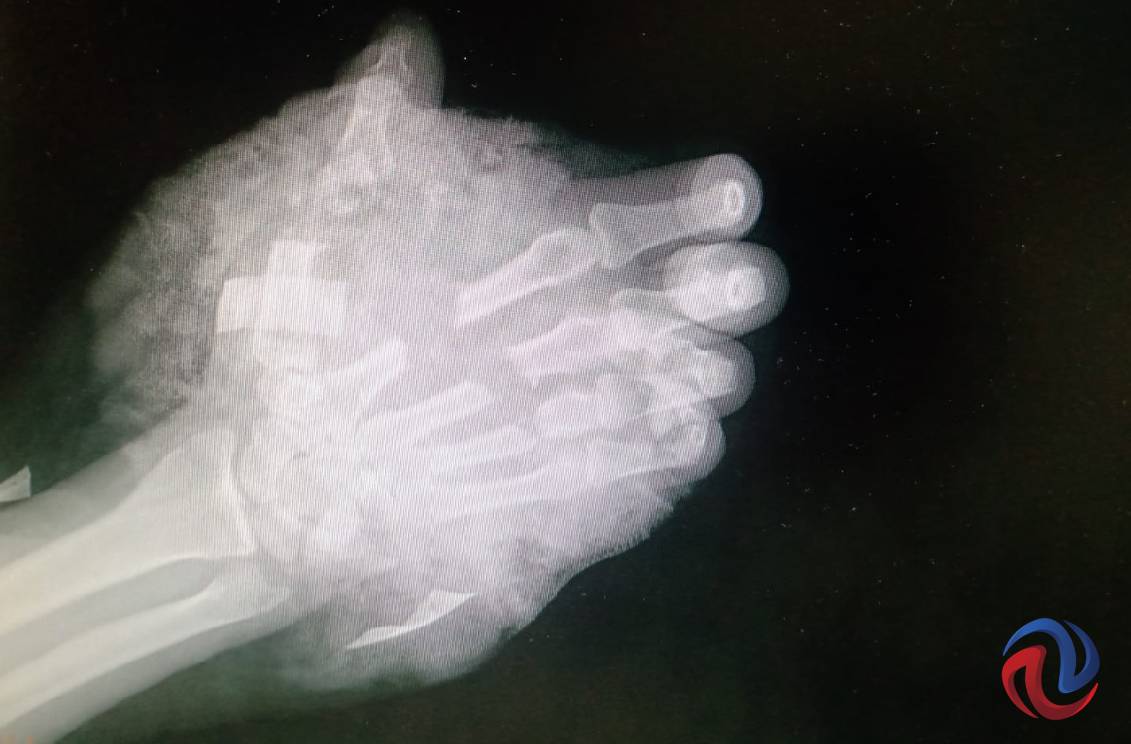

TIJUANA BC 30 DE JUNIO DE 2021 (AFN).- El pasado 15 de abril Horlando estaba a punto de concluir su trabajo, donde operaba una sierra para cortar metal, cuando en un movimiento inesperado el equipo alcanzó su mano derecha provocándole una herida tan grave que según el diagnóstico inicial le haría perder la extremidad. Hoy casi tres meses después no solo la conservó, sino que avanza rápidamente en la recuperación gracias a médicos del Instituto Mexicano del Seguro Social.

El sangrado era abundante y la apariencia de la herida dejaba ver que se trataba de una lesión grave, así que fue trasladado al área de urgencias del Hospital General Regional (HGR) No. 1, donde recibió los primeros auxilios y se detuvo la hemorragia.

También se aplicaron antibióticos y analgésicos para evitar una infección y combatir el dolor del paciente, mientras el personal médico seguía de cerca el comportamiento de la mano, y hubo un momento en que, por las características de la lesión, los médicos contemplaron la posibilidad de una amputación de la mano a la altura de la muñeca.

El equipo de traumatología del IMSS, sin embargo, valoró las opciones y tomó la determinación de estabilizar la extremidad lesionada y programar una cirugía reconstructiva. Los dedos afectados presentaban todavía circulación de sangre y esto significaba la esperanza de poder salvar la mano.